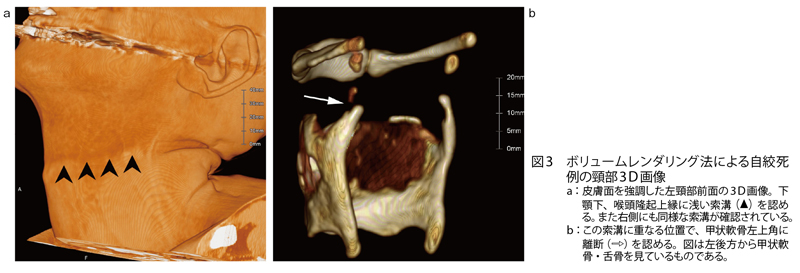

死亡時画像診断(Autopsy imaging)におけるチェックシートの